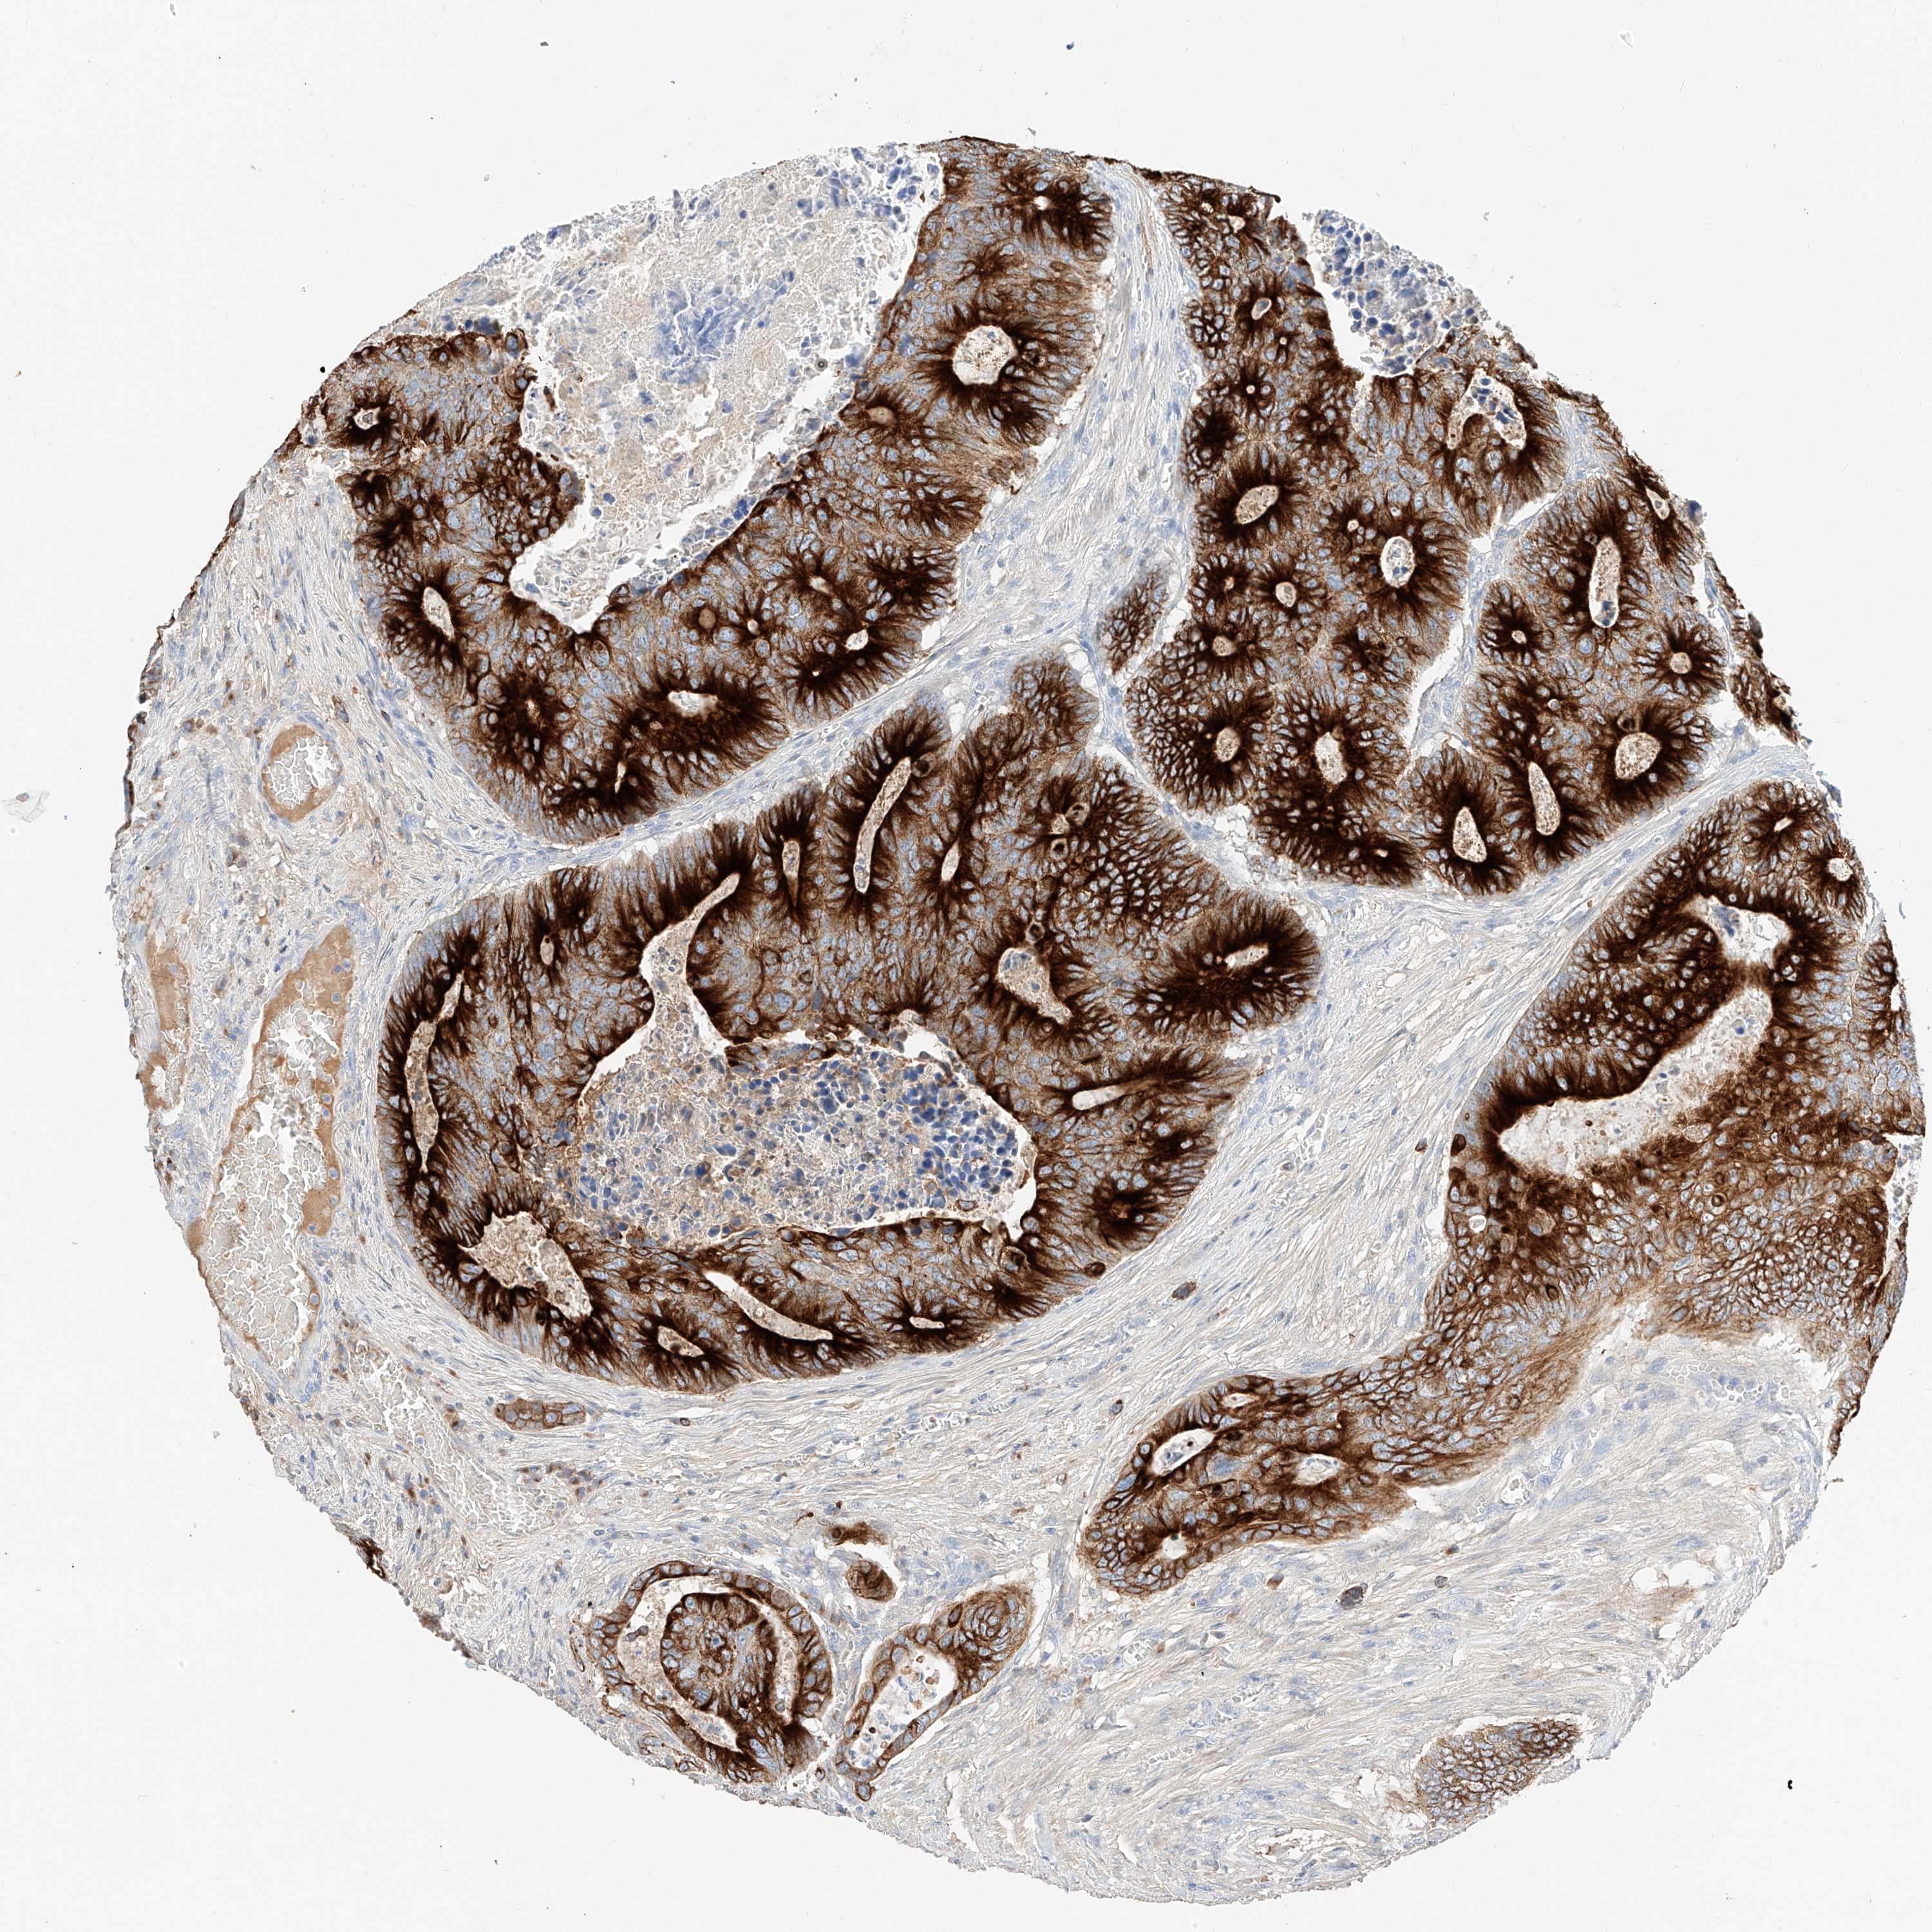

CANCER COLORECTAL CANCER Show tissue menu

COAD TCGA COAD VALIDATION READ TCGA READ VALIDATION PROTEIN COAD CPTAC PROTEIN EXPRESSION

ANTIBODIES

AND

VALIDATION